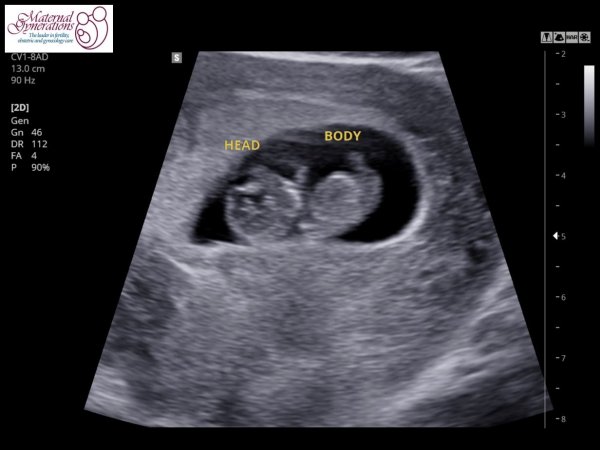

- شما ممکن است حرکت رویان خود را در سونوگرافی هفته ۱۰ ام ببینید. انتظار می رود که دست ها, پاها و سر رویان به وضوح دیده شود.

- از آنجایی که پوست رویان در این هفته شفاف است, شما احتمالا اندام های داخلی او را مشاهده می کنید.

- بر روی مانیتور, شما ضربان قلب رویان خود را مشاهده می کنید و همچنین می توانید آن را بشنوید.

- شما احتمالا برآمدگی پیشانی رویان را مشاهده می کنید. پیشانی به این دلیل برآمده شده است که بتواند با رشد مغز تطبیق یابد. اگرچه به تدریج این برآمدگی از بین می رود و تخت خواهد شد.

- استخوانبندی رویان تکمیل می شود و استخوان بندی ستون مهره نیز دیده می شود.